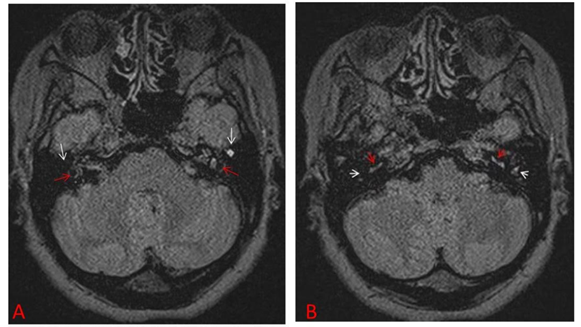

The biopsy with the lesion of the superficial epithelial masses of debris was performed. Microscopic examination showed the evidence of a fungal infection, tons of containing hyphae fungi were seen (Figure 2).

Figure 2 Tons of containing hyphae fungi seen under microscopic using HE stain (10x).